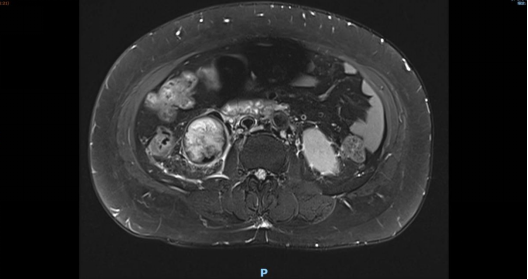

肾癌合并下腔静脉癌栓(Mayo Ⅲ级)

是泌尿外科极具挑战性的疑难重症,癌栓已侵入肝后段下腔静脉,紧邻重要血管与脏器,手术难度极大、风险极高,对术者技术、麻醉管理及多学科配合均有着严苛要求。

51岁的康女士半年前体检时发现存在肾囊肿,进一步检查确诊为肾癌,由于癌栓体积较大,已达到III级,直接手术存在较大风险,为最大程度保障治疗效果与患者长远生活质量,齐鲁医院德州医院泌尿外科副主任高立健,医院知名专家、主任医师谷振祥,主治医师张旋,医师朱红飞组成核心诊疗组,针对康女士情况进行全面评估,建议其先接受规范的术前靶向药物治疗。经过半年的精准靶向治疗,患者肿瘤负荷得到有效控制,为手术实施创造了有利条件。